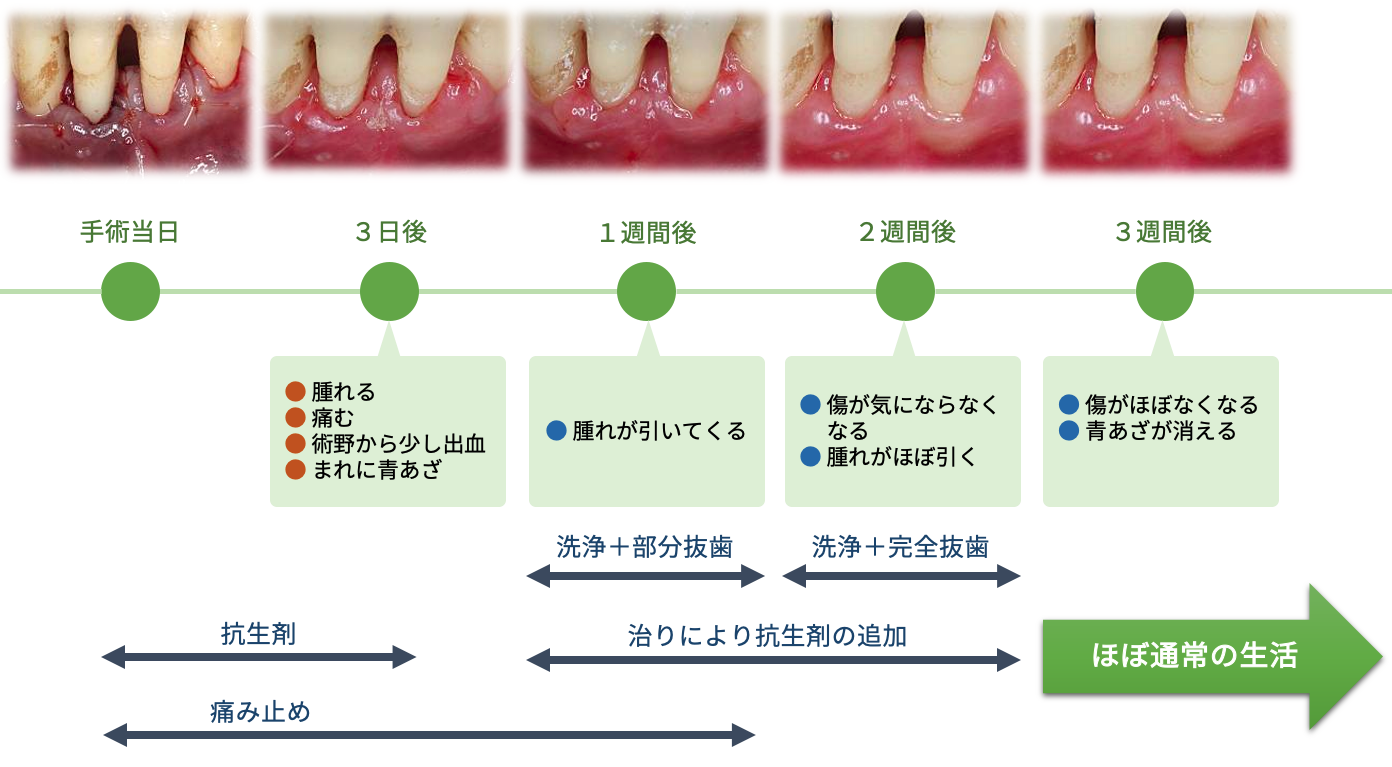

これは、虫歯や歯周病などで抜歯が必要になった際、その当日にインプラントを埋め込む方法です。従来であれば、抜歯後に歯ぐきや骨の治癒を数ヶ月待ったうえで次のステップへ進んでいましたが、この方法を用いることで、治療期間を短縮できるほか、手術の回数も抑えられます。

ただし、抜歯即時埋入はすべての患者さまに適応できるわけではありません。

炎症の有無や骨の状態、歯ぐきの厚みや形など複数の条件を慎重に確認する必要があります。

大杉歯科医院では、CTや口腔内検査によって十分な診査を行い、適応可能と判断できた方にのみご提案しています。